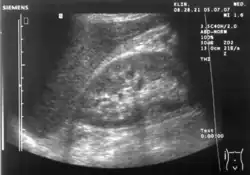

Abdominal ultrasonography (also called abdominal ultrasound imaging or abdominal sonography) is a form of medical ultrasonography (medical application of ultrasound technology) to visualise abdominal anatomical structures. It uses transmission and reflection of ultrasound waves to visualise internal organs through the abdominal wall (with the help of gel, which helps transmission of the sound waves). For this reason, the procedure is also called a transabdominal ultrasound, in contrast to endoscopic ultrasound, the latter combining ultrasound with endoscopy through visualize internal structures from within hollow organs.

Advantages of ultrasound imaging of abdominal structures are that the procedure can be performed quickly, bed-side, involves no exposure to X-rays (which makes it useful in pregnant patients, for example) and is inexpensive compared to other often-used techniques such as computed tomography (CT scan) of the abdomen. Disadvantages are troublesome imaging if a lot of gas is present inside the bowels, if there is a lot of abdominal fat, and that the quality of the imaging depends on the experience of the person performing it.